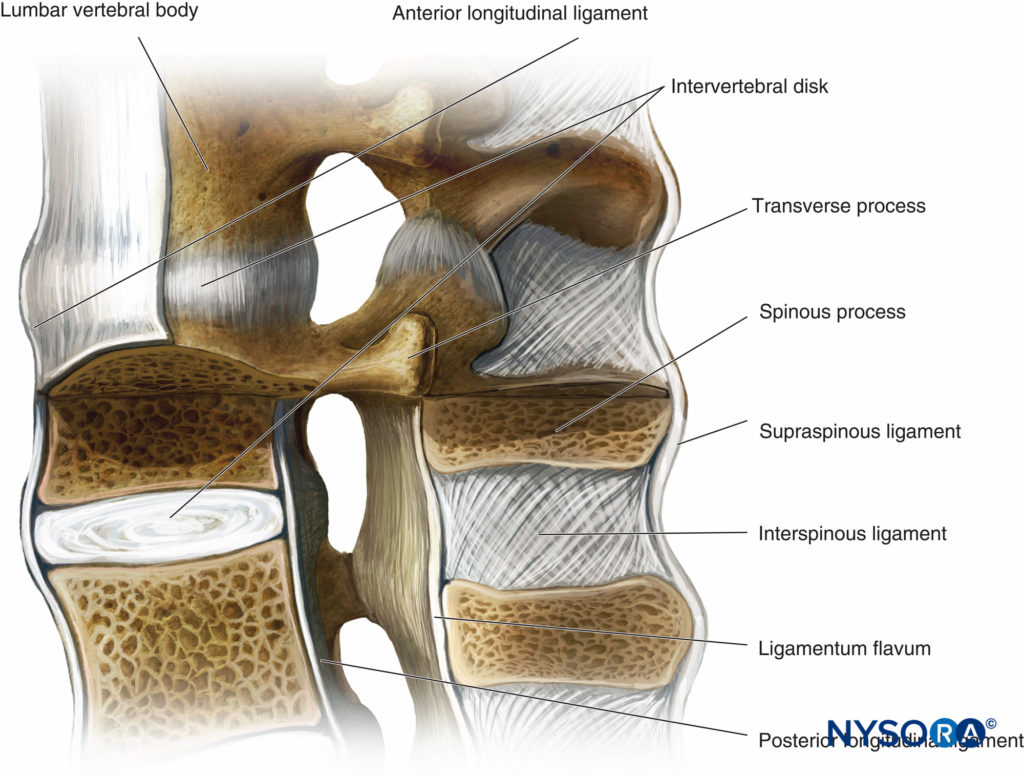

Pure Health - Anatomy 101 - Supraspinous ligament and interspinous ligament 📚 The supraspinous ligament and interspinous ligament work together to limit flexion of the spine by limiting separation of the spinous

DOCS - The interspinous ligament is located between the spinous processes of adjacent vertebrae in the spine. It extends from the base of one spinous process to the apex of the next,

Anatomy of the vertebral column and spinal cord (Chapter 55) - Essential Clinical Anesthesia Review